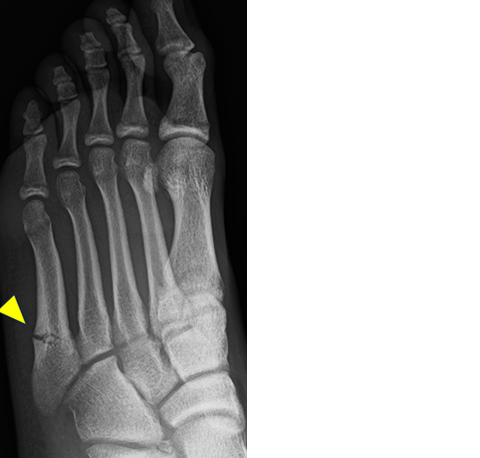

2) ジョーンズ骨折(第5中足骨疲労骨折)

第5中足骨近位部(からだに近い部分)に発生する疲労骨折で、治りにくく、また再発も多い骨折です。サッカー選手に多く、足のアライメント(形)、関節柔軟性の低下(特に股関節内旋)、足趾把持力の低下、スパイクシューズの形状、人工芝などが原因とされています。早期に診断されれば、治療しながらプレーすることも可能ですが、完全骨折に至った場合は手術を要することもあります。

単純X線